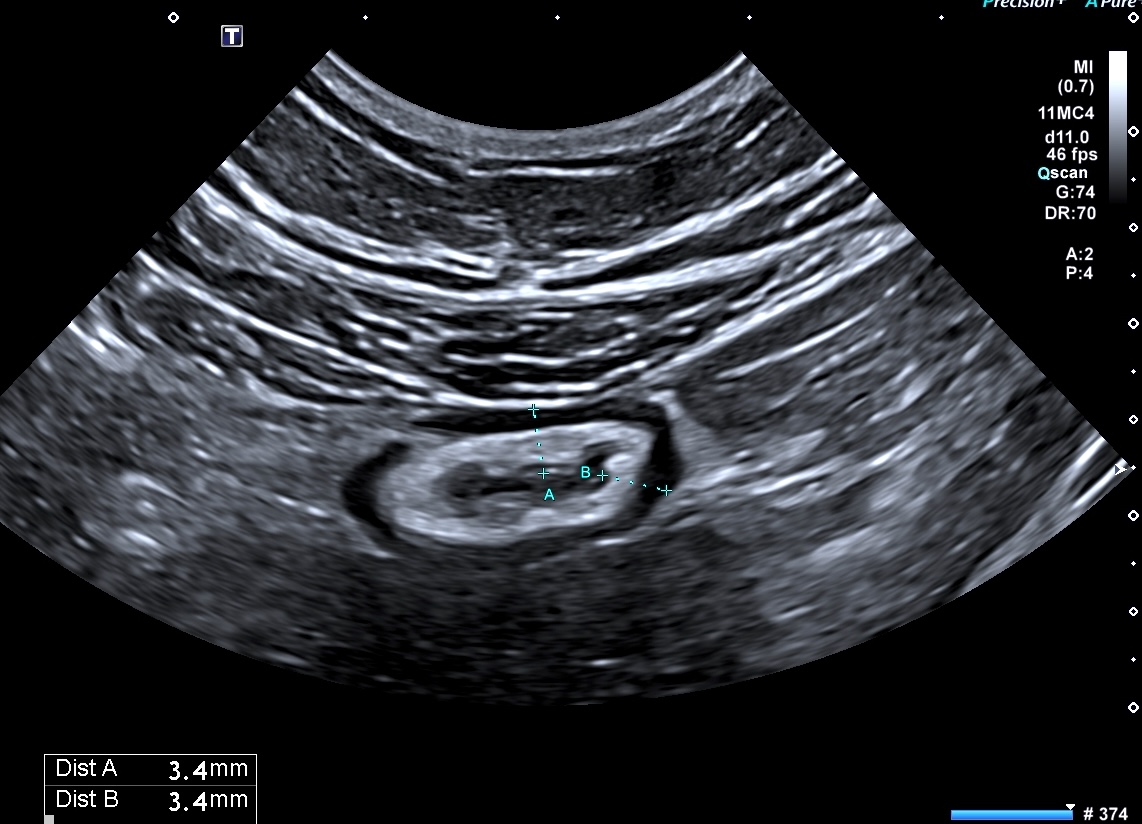

Muqueuse épaissie en coupe transversale

L'épaississement prédomine à la 3 ième couche hyperéchogène( > 1/3 de la paroi), il est continue, régulier, cironférentiel

La structure en couche est conservée

La graisse est peu infiltrée, l'activité doppler modérée.